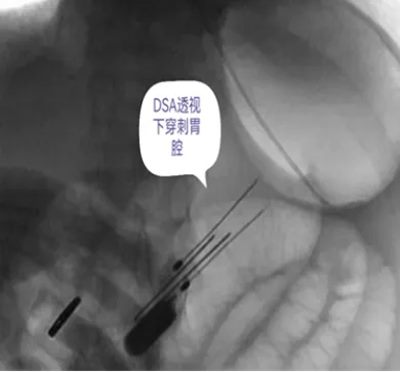

DSA引导下经皮胃造瘘术,是在数字减影血管造影(DSA)这个“透视眼”的实时可视化导航下,于患者腹壁上建立一个仅 3-5毫米 的微小穿刺点。通过这个“针眼”,医生精准地将一根营养管直接置入胃部,建立起一条直达的营养通道。

整个过程就像一次精准的“导航穿刺”,全程操作便捷、创伤小,却能完美替代传统的鼻饲管,为患者提供长期、稳定、安全的营养支持。

医院临床实践中就有典型案例:一名65岁食道癌伴淋巴结转移患者,因食道狭窄无法插入胃镜,且体质虚弱难以耐受全麻手术,团队借助DSA精准导航,仅用10分钟便完成手术,局部麻醉下患者全程无明显不适,术后1天即可通过造瘘管补充营养,为后续抗肿瘤治疗顺利开展奠定了坚实基础。